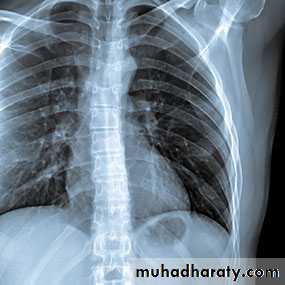

Interstitial lung disease

Lab monitoring every 4-8 wks CBC, LFTs, CreatinineToxicities: hepatic, myelosuppression, pulmonary